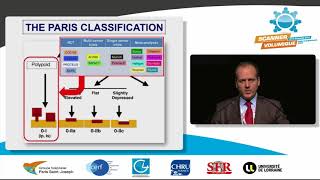

coloscanner V.S scanner standard

Enteroscanner V.S scanner standard 4 -Colo scanner : où en sommes nous ?

4 -Colo scanner : où en sommes nous ? difference entre un coloscanner et un scanner abdominale standard

coloscanner V.S scanner standard

Enteroscanner V.S scanner standard 4 -Colo scanner : où en sommes nous ?

4 -Colo scanner : où en sommes nous ? difference entre un coloscanner et un scanner abdominale standard